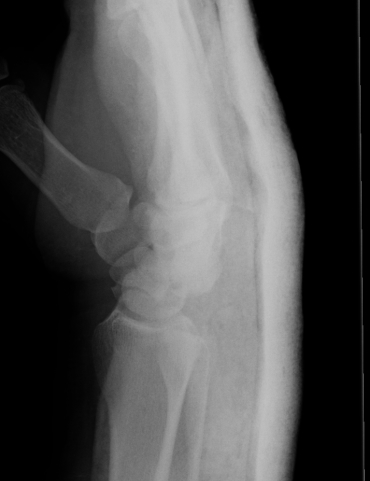

X-ray

Disruption of Gilula's 3 smooth carpal arcs

Progressive Injury

1. Capitate dorsal

- lunate remains with radius

- lunate looks triangular on AP

2. Lunate dislocates

- usually volar